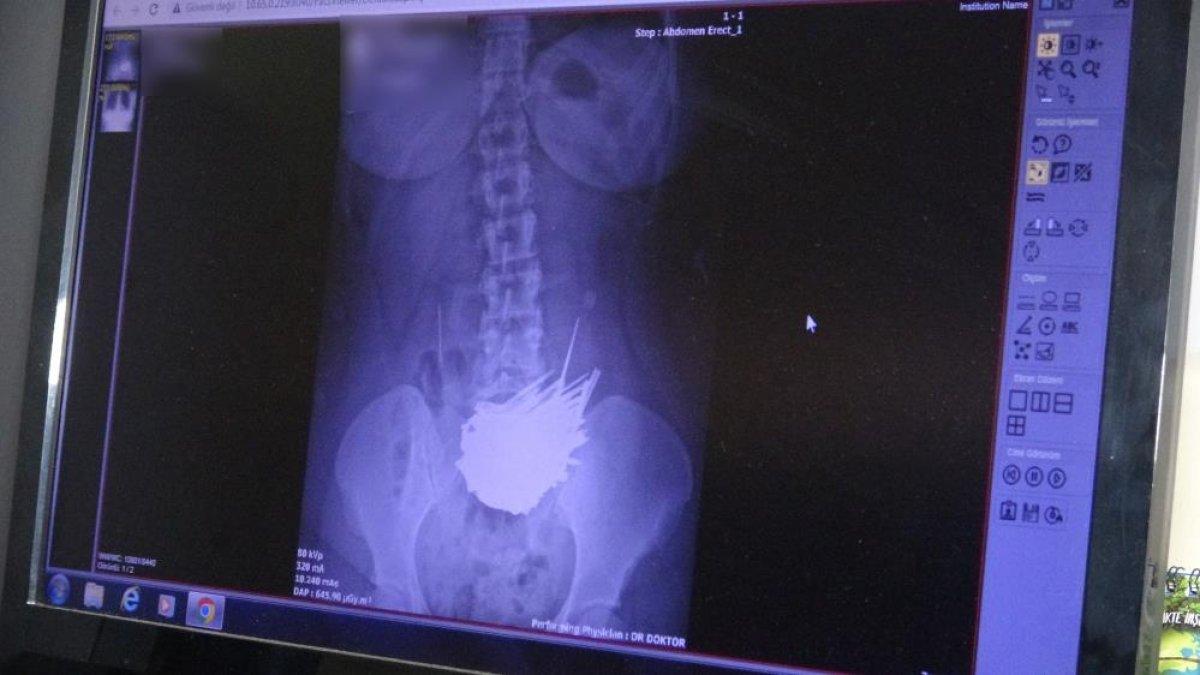

Burada yapılan tomografi sonrası hastanın midesinde tel ve bazı yabancı cisimlerin olduğu rapor edildi.

Ameliyata alınan genç kadın hastanın midesinden tırnak makası, çakı, meyve bıçağı, cımbız, çivi, iğne, çuvaldız, tığ, vida, çengelli iğne, anahtar, madeni para, saç tokası gibi metal parçalarıyla plastik ve cam parçaları çıkarıldı.

Meyve bıçağı gibi kesici cisimlerin bir poşete sarılı vaziyette olması ise doktorların dikkatini çekti. Midesinden çıkan 158 cisimle doktorları hayrete düşüren hasta, sağlığına kavuşmasının ardından taburcu ediliyor.

Tomografi sonucunda iğneyle birlikte yabancı cisimler de tespit ettiklerini ifade eden Dr. Tekeş, “Midesinde bu kadar büyük bir şey beklemiyorduk. Tomografi filmleri çektik. Ameliyatta mideyi açtığımızda çeşitli yabancı cisimlerle karşılaştık. Yabancı cisimleri görünce çok şaşırdık. Hastamızın sağlık durumu iyi. Ameliyat sonrası çekilen röntgenlerde ise yabancı cisme rastlanmadı” dedi.